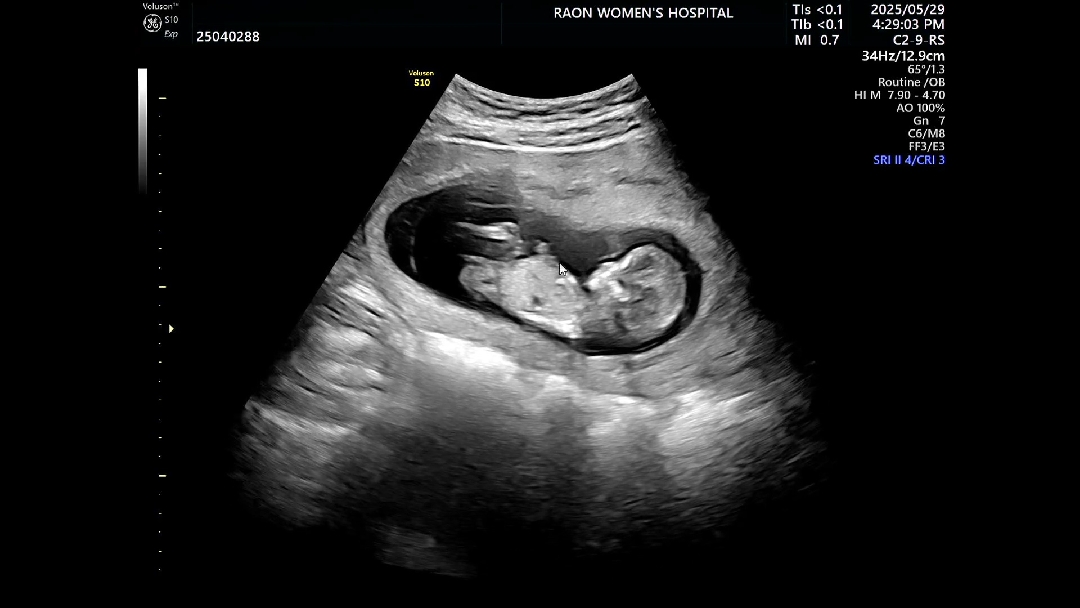

12주차 아가 초음파에요!! 아들일지 딸일지 너무너무 궁금해요🥹 둘다 너무 감사한 축복이지만, 남편은 아들, 저는 딸 바라기 중인데요!! 저에게 희망을 주세요...👉👈 아들, 딸 어떻게 보이시나요~~?!!